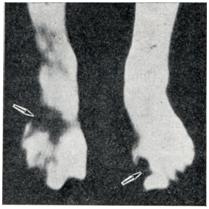

При отморожении III и IV степени после развития реактивных процессов формируются три зоны: тотального некроза, демаркационного воспаления, восходящих дистрофических и очаговых некротических изменений (рис. 7). Наиболее глубокие изменения локализуются обычно в дистальных участках конечности. Однако может иметь место и гнездное расположение очагов деструкции, когда участки некроза располагаются также в проксимальных отделах конечности (рис. 8).